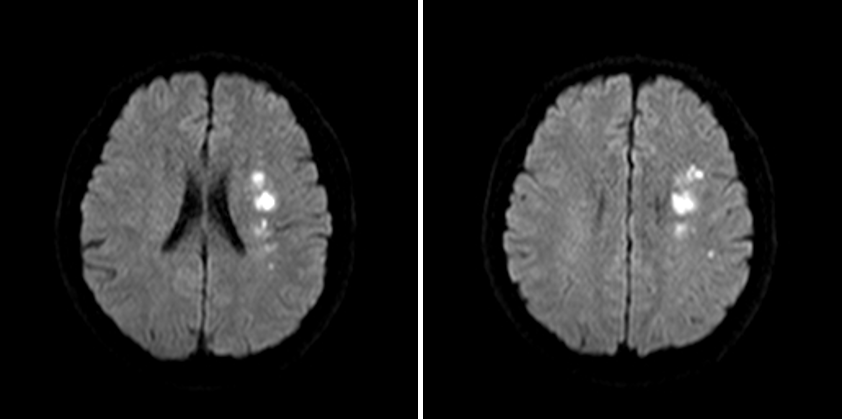

MRA

DWI

重要影像结论:左基底节区、放射冠区脑梗死,左大脑中动脉M1末端狭窄。

重要影像结论:左基底节区及放射冠区脑梗死。